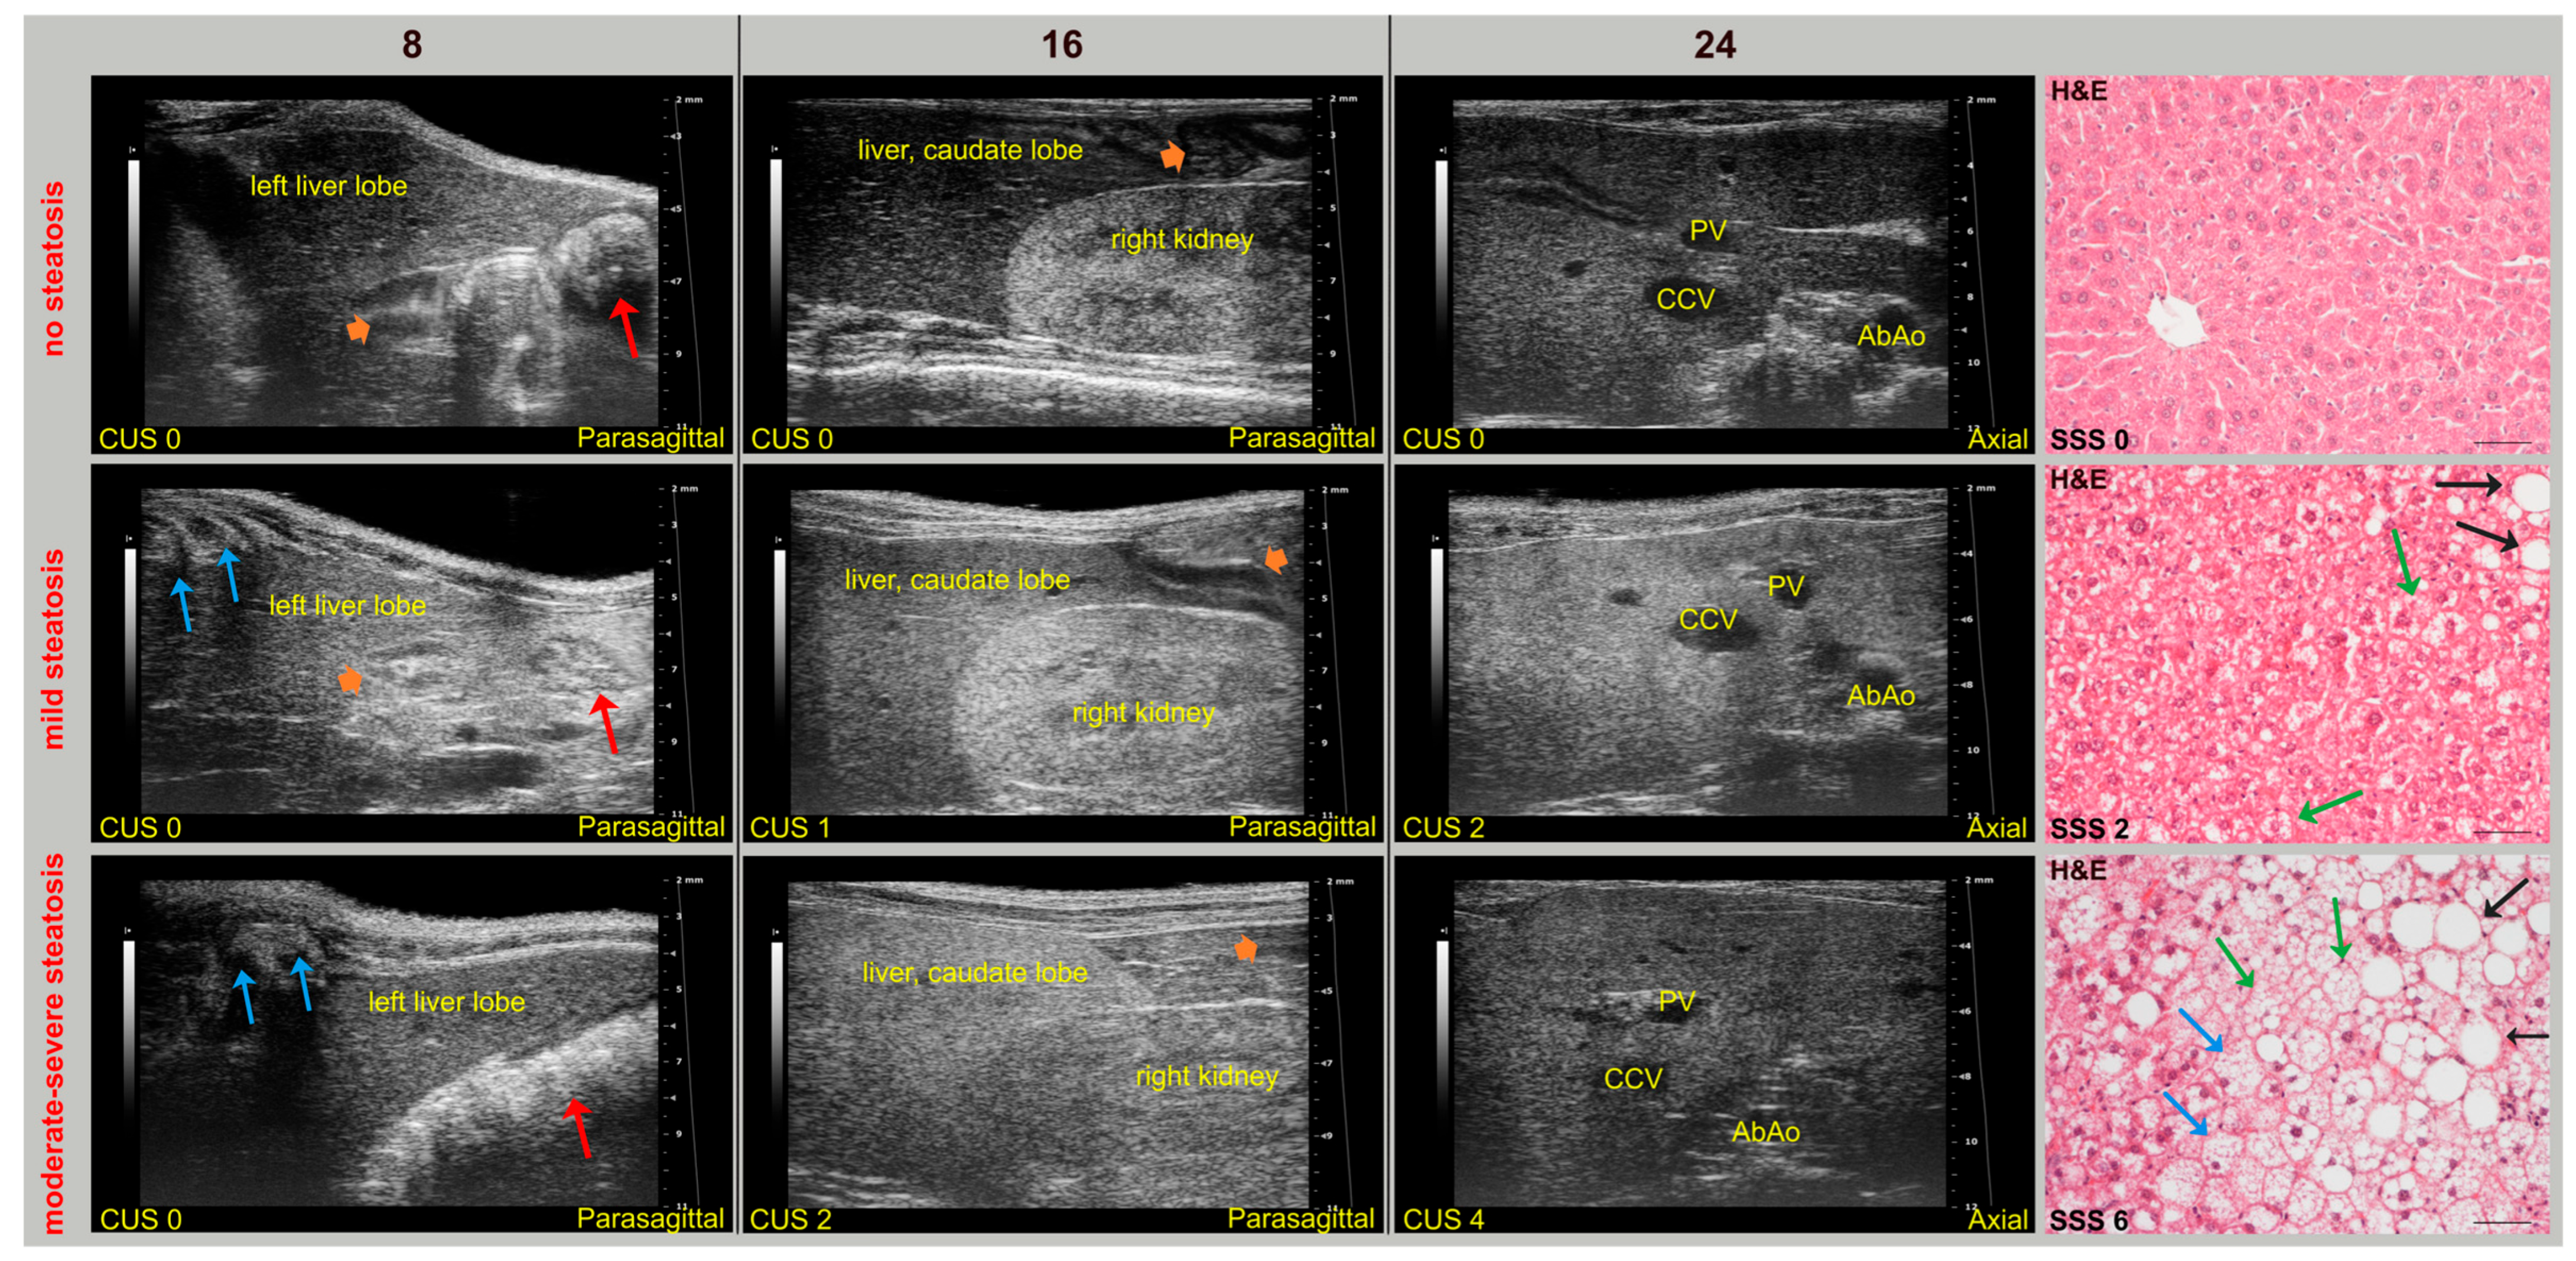

During imaging sessions, body temperature, heart, and breath rates were monitored and normothermia was maintained using a heated platform and an infrared lamp. Mice were anesthetized with inhalant gases (induction chamber: 4% isoflurane plus 2 Lt/min oxygen; maintenance with nose cone: 1.5–1.8% plus 2 Lt/min oxygen). Subsequently, the mice were placed in a supine position and a coupling gel was applied to the trichotomized skin. US two-dimensional (2D) B-mode images of the liver of mice (left, right, and caudate lobes, sagittal and axial planes) at 8 (baseline, pre-diet), 16, and 24 weeks of age were acquired in real time by a veterinary radiologist with 17 years of experience (SG) (

Figure 1). A dedicated HFUS equipment was used (Vevo 2100, FUJIFILM VisualSonics Inc., Toronto, ON, Canada; MS550 transducer: central frequency 40 MHz; focal length 6 mm; depth of penetration 5–15 mm; 30–40 µm axial and 70–90 µm lateral resolution). The time gain compensation and other operating parameters were kept constant throughout experiments (frequency = 40 MHz, frame rate = 16 images/s, gain = 30 dB, depth = 11 mm, width = 13.00 mm, dynamic range = 60 dB, sensitivity = high; transmit power = 100%) to avoid experimental bias. Each liver HFUS acquisition, including overall animal preparation, took no more than 15 min. During recovery, all animals were monitored for any signs of pain or discomfort.

63]. Indeed, mild-to-moderate hepatic steatosis was confirmed by histology in three SD-fed KO mice (43%), which exhibited corresponding changes in US features over time. In particular, histology-confirmed US findings of steatosis started to appear at 16 weeks of age in both WT (62.5%) and KO (100%) mice fed WD, with overall higher severity in KO mice. Additionally, HFUS images were examined to detect renal abnormalities. In agreement with biochemical tests, no mouse showed an abnormal US renal appearance, with clear visualization of the corticomedullary border, renal papilla, and echogenic renal capsule. Representative HFUS liver views and related histological images are provided in

Figure 4.